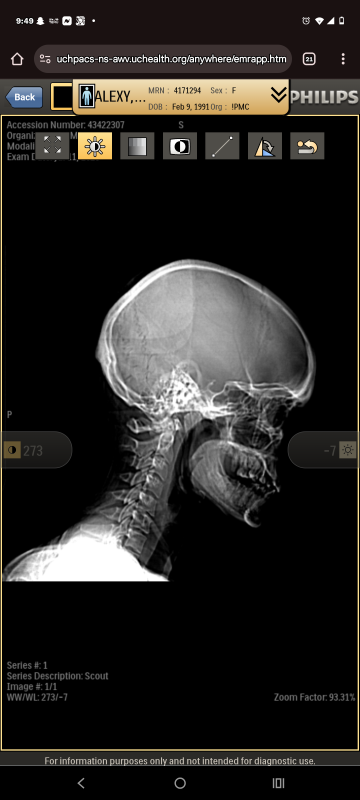

My name is Jessica I am 34 yrs old single mom, I have been working for the past 6 years full time and getting my business and accounting degree, however the last 2 months . I began having seizures again. However this one was the worst ,I fell and busted my entire face, and my heart stopped and had no pulse. I was in the hospital for 3 day and lost my job. Now I am on medication I cannot drive, be alone etc. I have a 1 year old son and 10 year old daughter. I have been struggling with what I can do . I haven't been able to get my disability yet as I am still waiting on the paper work to go through and I have my appointments for the MRI and EEG coming up on the 30th, they found a blood vessel that's is narrowing in my brain and what causing them and can cause strokes if not addressed quickly. the neurology appt is out a few months. In the mean time I have no insurance as I was insured through work but no longer am. Waiting in limbo for medicaid, but cannot get my medication which is why I am continuing having them . I am now behind on a few bills, and one month of rent,. I have lived here for almost 3 years now. as well as the things we are needing. such as diapers, wipes, baby food, school supplies. hygiene I have no choice but to ask for help. I have never been in a situation where I haven't been able to fully cover all our needs and wants. Until now and its out of my control. I don't want to lose our home while I am waitng for my disability. I am scared. I have reached out for assistance in my area and the few places are low on funding I was told call back in a month , by then It will be too late , I feel like I am failing my family and letting my kids down. I've become so much more depressed, which is making everything harder to manage . I will have attached photos of proof and happy to verify any other questions . I'm not trying to ask for alot just enough to get us by until I get my disability going. anything helps even prayers and good vibes sent our way . Thank you for reading this far and thank you for any thing you can do. I am more greatful than you'll even know. Sincerely Jessica Alexy I have cash app or chime if that matters, I have never done this before so I'm not sure how it works. if any questions need answers feel free to email or text [email protected] 7195047981